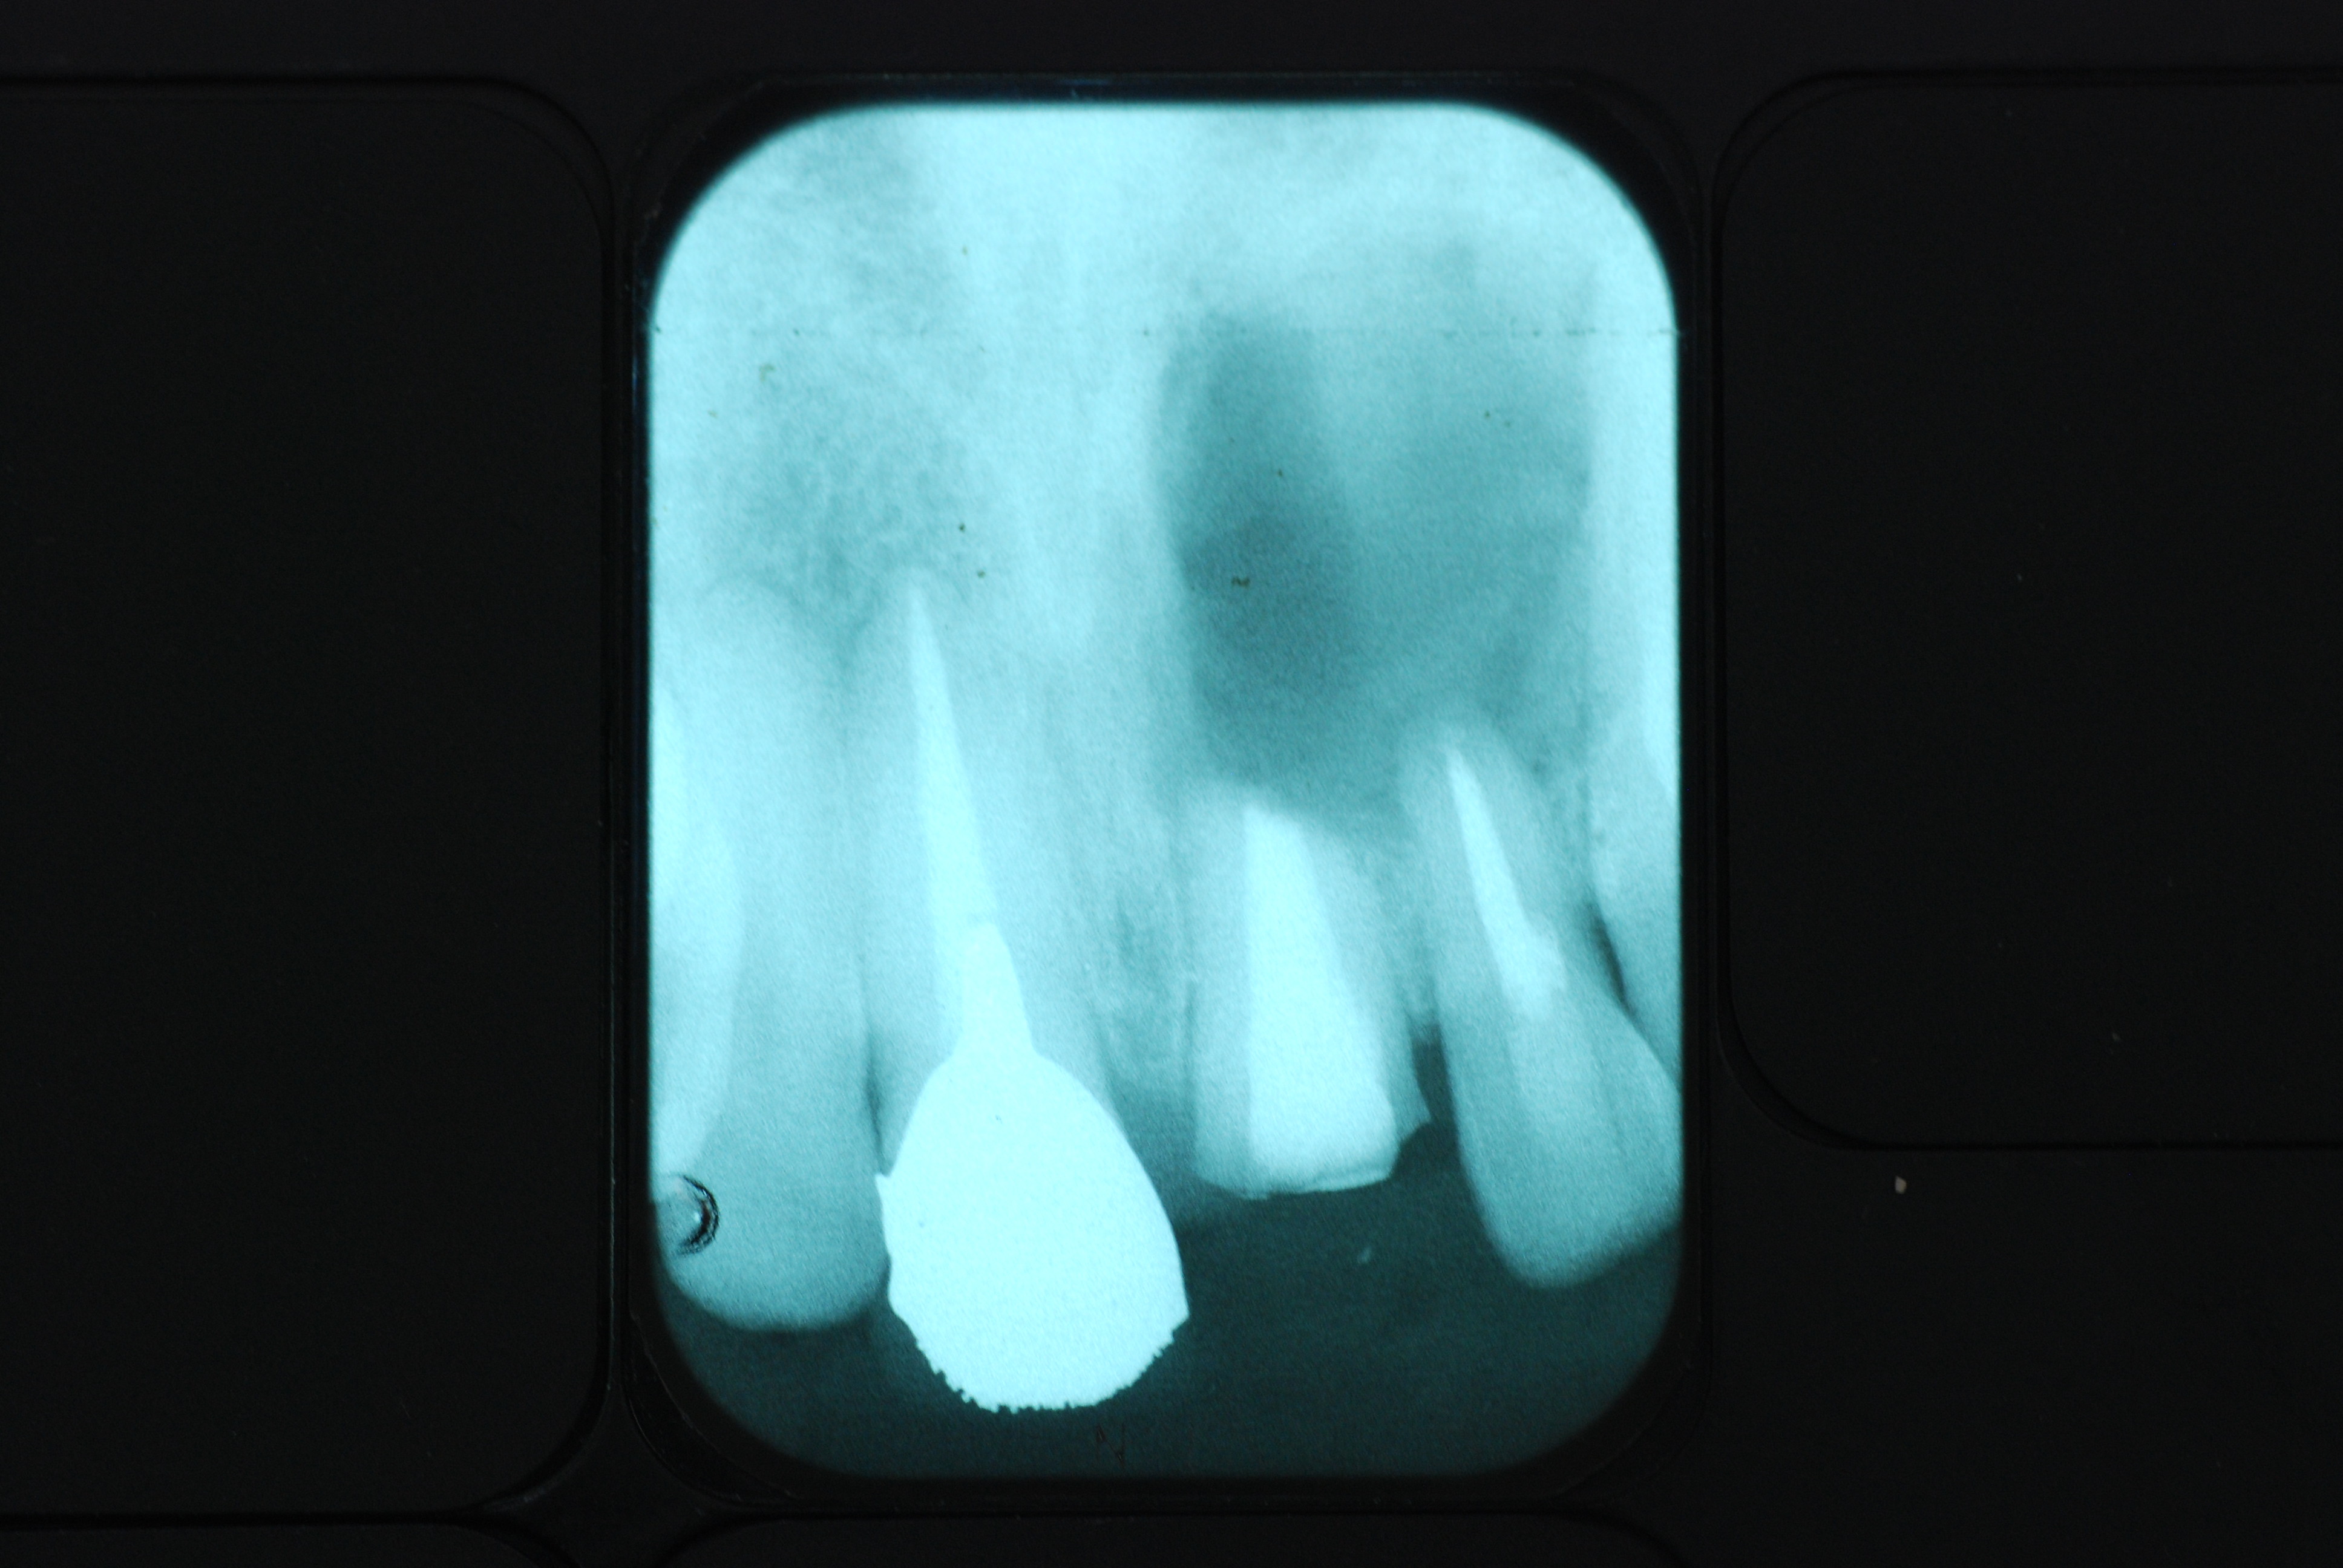

必ずばい菌が侵入しないようにしてばい菌である虫歯を除去します。

銀歯の下はばい菌だらけです。こういうのはよくあります。取り残しですね。![treatment_05[1]](https://livedoor.blogimg.jp/netdental/imgs/3/a/3ad019d0-s.jpg)